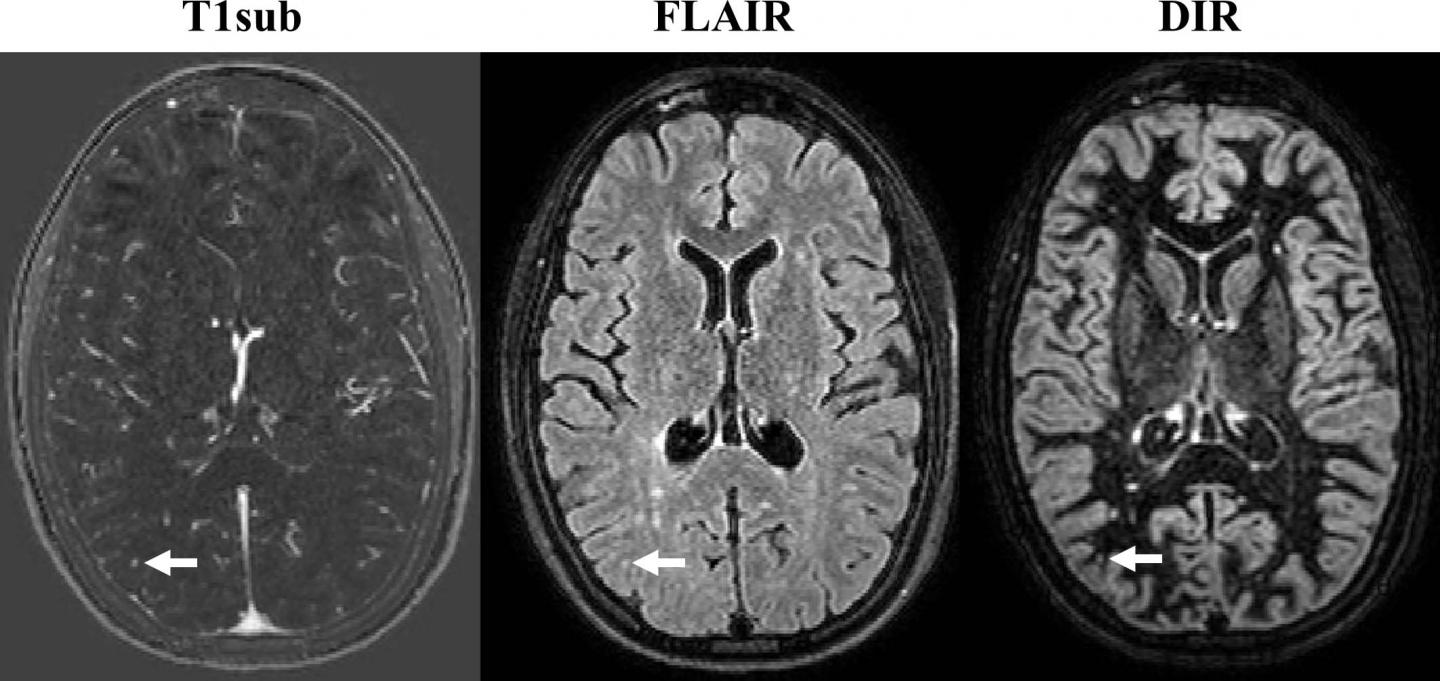

If multiple sclerosis diagnosis takes place early, the what are the causes and symptoms of multiple sclerosis? It's a lifelong condition that can sometimes cause serious disability, although it can occasionally be mild. Multiple sclerosis can cause a variety of symptoms: Symptoms often affect movement, such as: Multiple sclerosis (ms), also known as encephalomyelitis disseminata, is a demyelinating disease in which the insulating covers of nerve cells in the brain and spinal cord are damaged. Residents and fellows contest rules | international ophthalmologists contest rules. Multiple sclerosis, or ms, is a disease of the central nervous system that can cause symptoms throughout the body. An overview of multiple sclerosis (ms) including aetiology, clinical features (symptoms, signs) multiple sclerosis (ms) is an autoimmune inflammatory disease of the central nervous system (cns) which dissemination in time, demonstrated by mri/second clinical attack or presence of oligoclonal. Axial magnetic resonance imaging (mri) of a 30 year old man with relapsing remitting multiple sclerosis (ms) showing multiple periventricular lesions: The treatment objectives of ms include the prevention or reduction of new manifestations, hindering the progression of the disease, halting disease activity, improvement of symptoms, and improvement of quality of life. Since mri scans became available, other tests are now. (c) fluid attenuated inversion recovery (flair) image. Difficulties with coordination and balance;